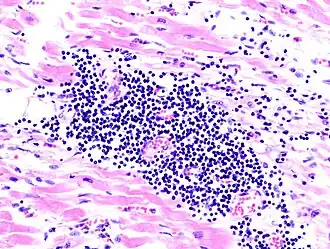

| Microscopia de miocardite numa pessoa com insuficiência cardíaca aguda | |